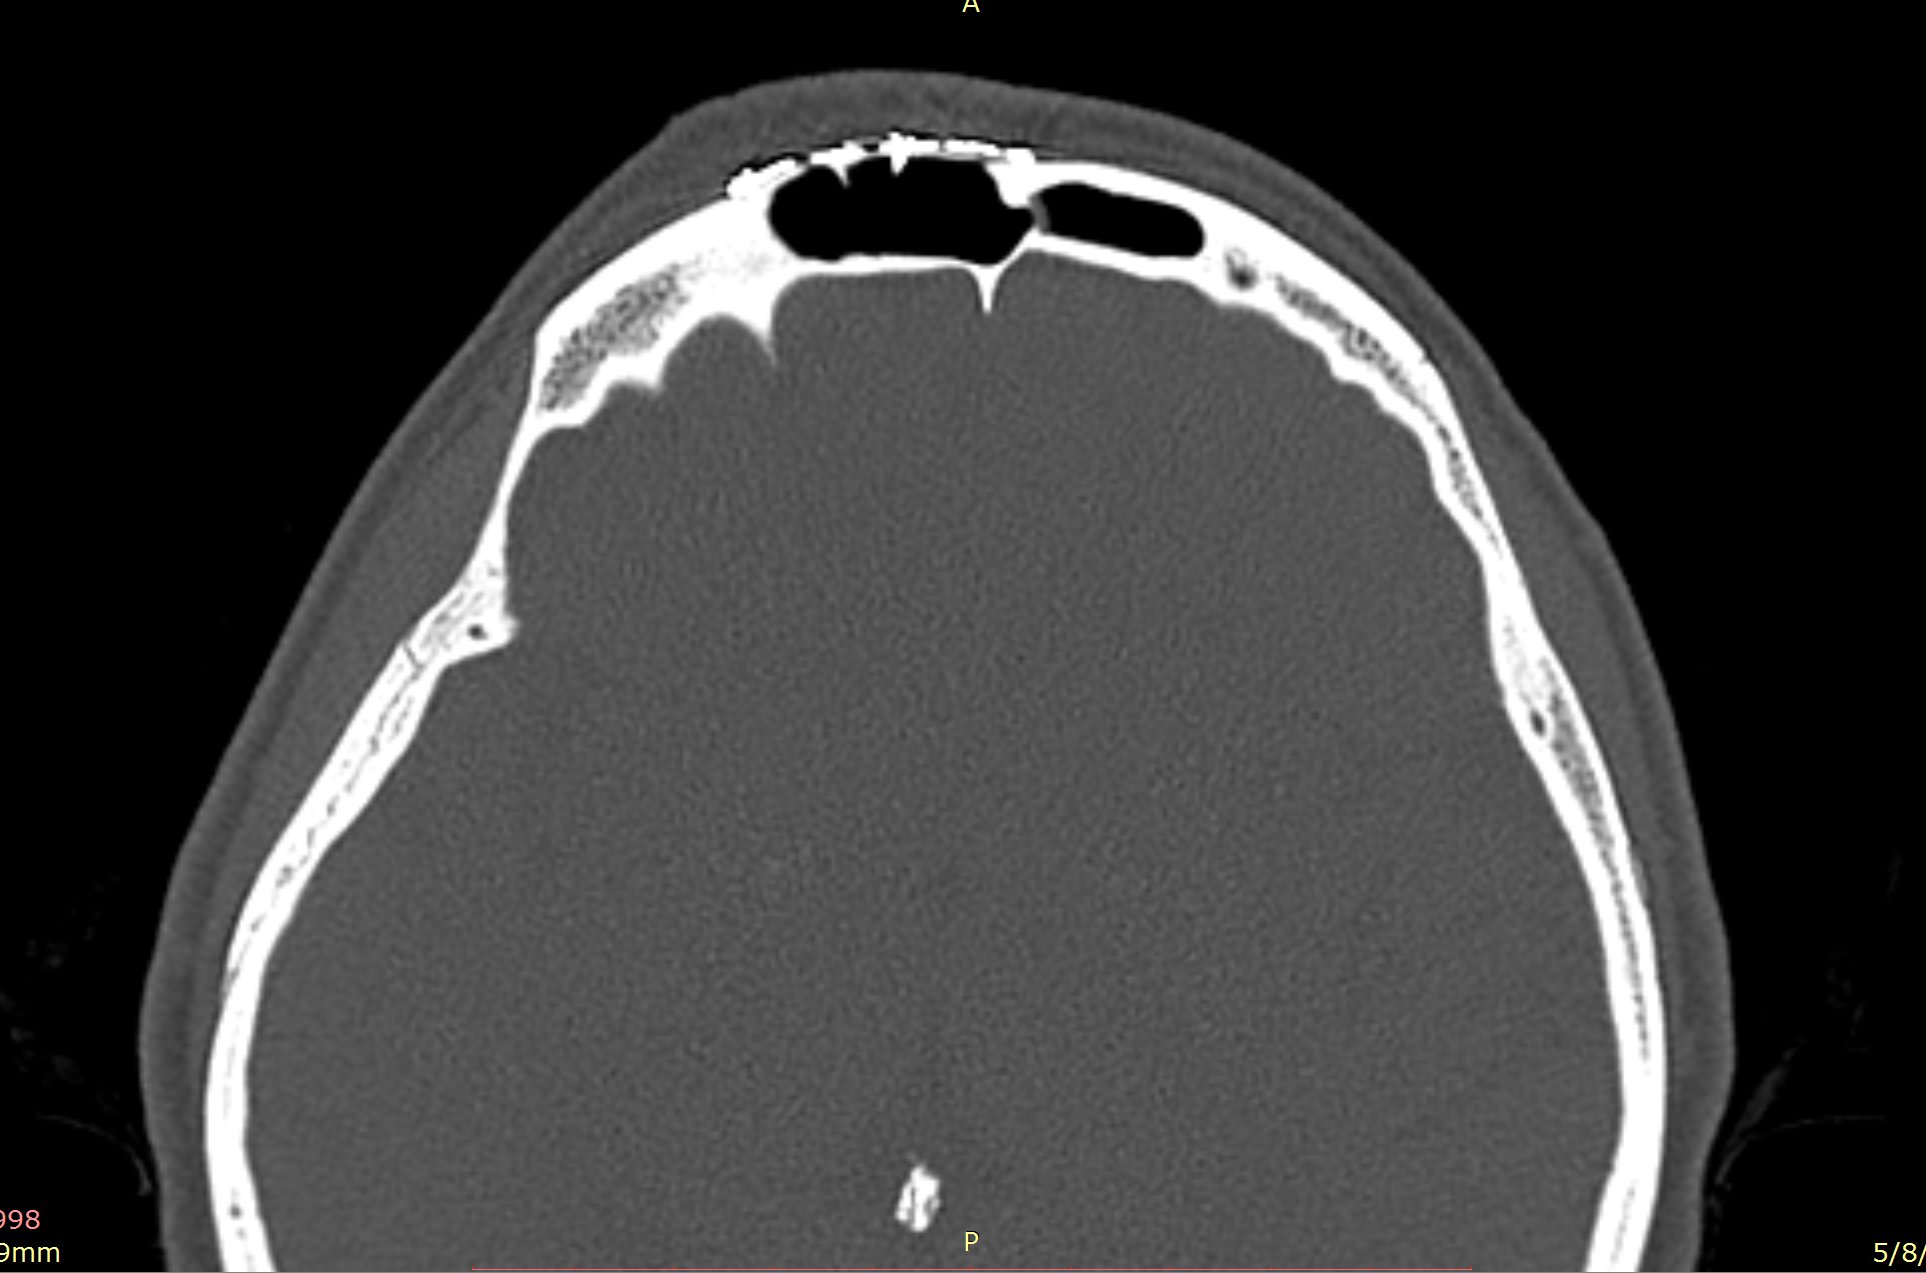

Examenul clinic ORL și examenele imagistice complementare (CT, RMN sinusuri paranazale) pun în evidență o formațiune tumorală osteogenică a sinusului frontal drept, protruzivă în unghiul supero-intern al orbitei, extinsă medial către sinusul frontal stâng.

Ziua 1 postoperator, pacienta efectuează CT sinusuri paranazale de control care certifică ablația completă a formațiunii.